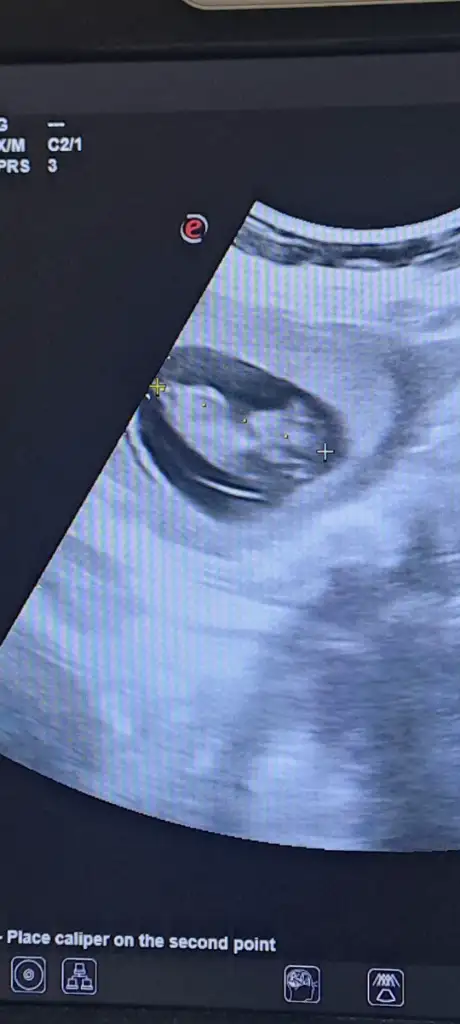

Canım erkeğe benziyor belli mi simdi cinsiyeti ne zaman belli olacakMerhaba kızlar cinsiyet tahmini yapabilen var mı acaba 13 haftalık ikiz gebelik birinin cinsiyeti öğrendik ama bu miniginkini doktorumuz daha var dedi. Tahminleri alayım? Eki Görüntüle 3582600

Alttaki erkek üstteki kız gibi geldi banaMerhaba kızlar cinsiyet tahmini yapabilen var mı acaba 13 haftalık ikiz gebelik birinin cinsiyeti öğrendik ama bu miniginkini doktorumuz daha var dedi. Tahminleri alayım? Eki Görüntüle 3582600